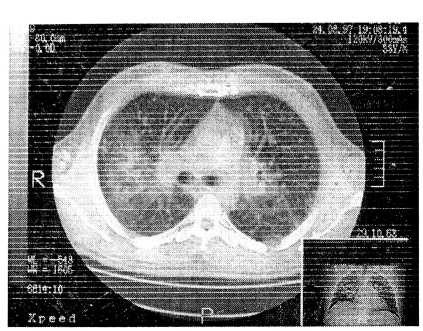

На рис. 2 и 3 представлены РКТ больного Д., 33 лет (саркоидоз II стадии, верифицированный трансторакальной биопсией) с интервалом в 2 года, который получил короткий курс системных стероидов с переходом на ингаляционные. Отмечена регрессия процесса.

Рис. 2. Рентгеновская компьютерная томограмма больного Д., 32 лет, при выявлении у него саркоидоза II стадии.

Рис. 3. Рентгеновская компьютерная томограмма больного Д., 32 лет, спустя 2 года наблюдения. Проведено лечение системными и ингаляциоными кортикостероидами. Достигнута регрессия процесса, которая была подтверждена улучшением параметров внешнего дыхания.